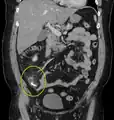

A fecalith marked by the arrow which has resulted in acute appendicitis.

A fecalith is a stone made of feces. It is a hardening of feces into lumps of varying size and may occur anywhere in the intestinal tract but is typically found in the colon. It is also called appendicolith when it occurs in the appendix and is sometimes concomitant with appendicitis.[1] They can also obstruct diverticula. It can possibly form secondary to fecal impaction. A fecaloma is a more severe form of fecal impaction, and a hardened fecaloma may be considered to be a giant fecalith. The term is from Greek líthos=stone.[2]

A small fecalith is one cause of both appendicitis and acute diverticulitis.